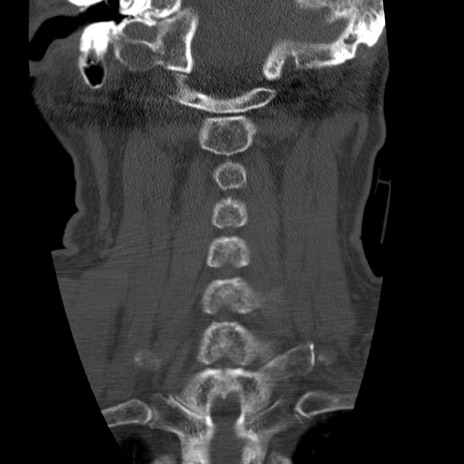

症例50 頚椎CT(冠状断像)

頚椎CT